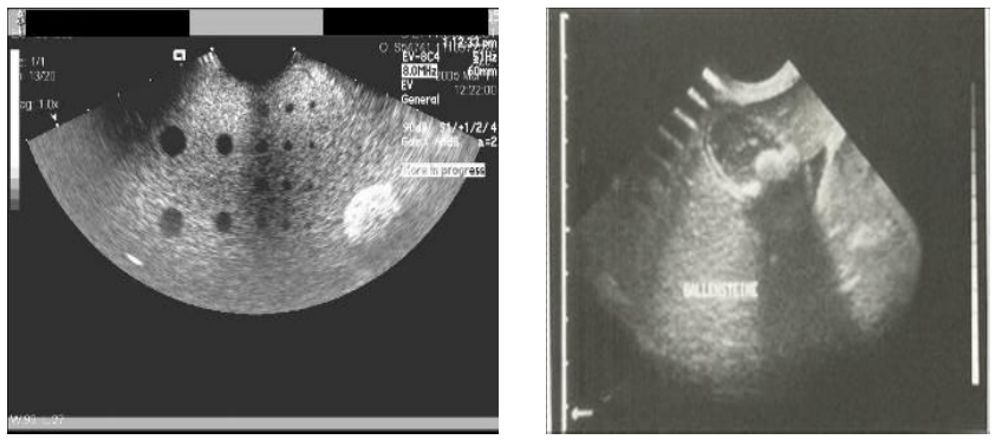

B超探头里信号没有输入输出,会导致显示区有暗道,可能有以下原因: ①探头的晶片中的某一个振片坏掉。 ②传送信号的电缆线断掉。 ③信号板铜皮线路或过孔由于某种原因不通。 ④信号板芯片虚焊或烧坏等等。

③探头屏蔽线及地线没接地或断了,导致机器受干扰。 B超探头所采用的电缆是质量要求很高的多芯高屏蔽电缆,做工十分精细,电缆内导线严密,多的有上百根,似发丝粗细。由于探头多方位的使用,电缆的弯曲、扭转使得电缆的外保护区绝缘层会破皮、断裂、露出了里面的信号线,屏蔽层的破坏、断线,图像就会产生干扰的波纹和缺损,继而导致图像显示模糊。